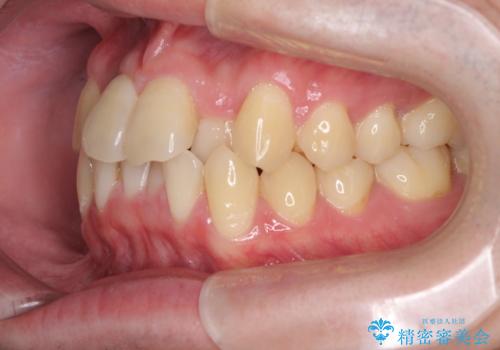

前歯のクロスバイト インビザラインによる矯正治療

- 上下のクロスバイトと前歯のデコボコを気にして来院された患者様です。

インビザラインを用い、IPR(歯と歯の間を削る)と歯列全体を拡大させることで、歯並びを整えていくこととしました。

上下ともに歯列全体を後方に移動させるため、上下の親知らずを抜歯することとしました。

奥に位置していた上の前歯が下の前歯を乗り越える際、奥歯でものを咬むことができず、辛い時期が続きました。